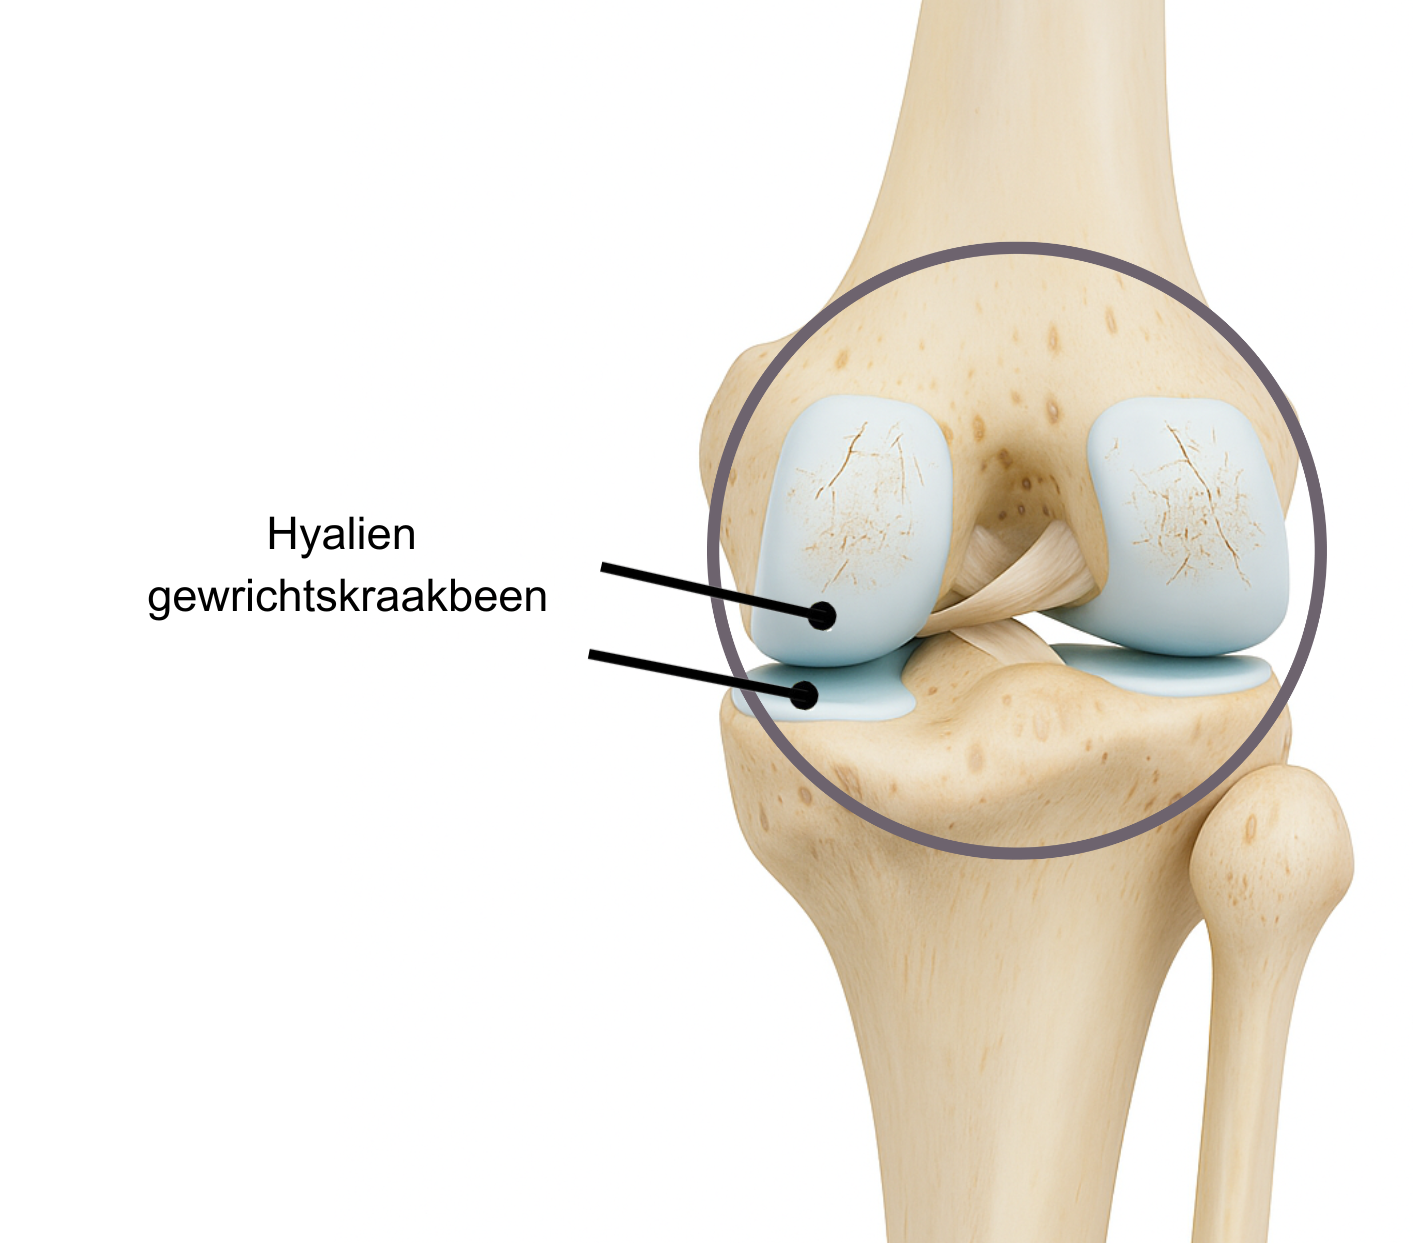

In elk gewricht zijn de uiteinden van de botten die met elkaar in contact staan bedekt met een laag hyalien gewrichtskraakbeen. Dit kraakbeen heeft een gladde, maar stevige structuur en zorgt voor de afgifte van synovia, een stroperige vloeistof die het gewricht smeert. Hyalien kraakbeen heeft twee belangrijke functies:

- Het soepel laten bewegen van het gewricht;

- Het opvangen van schokken en drukbelasting.

Zonder deze beschermende kraakbeenlaag zouden de botten te veel wrijving en belasting ondervinden, waardoor ze snel zouden beschadigen. Hoewel hyalien kraakbeen sterk is, heeft het maar een beperkt vermogen om te herstellen bij beschadiging of veroudering. Dit proces van natuurlijke achteruitgang wordt ook wel degeneratie genoemd. Artrose is een aandoening waarbij dit kraakbeen geleidelijk afbreekt. Als gevolg hiervan kan het gewricht stijf, pijnlijk, gezwollen en warm aanvoelen. In een later stadium kan ook het onderliggende bot worden aangetast.